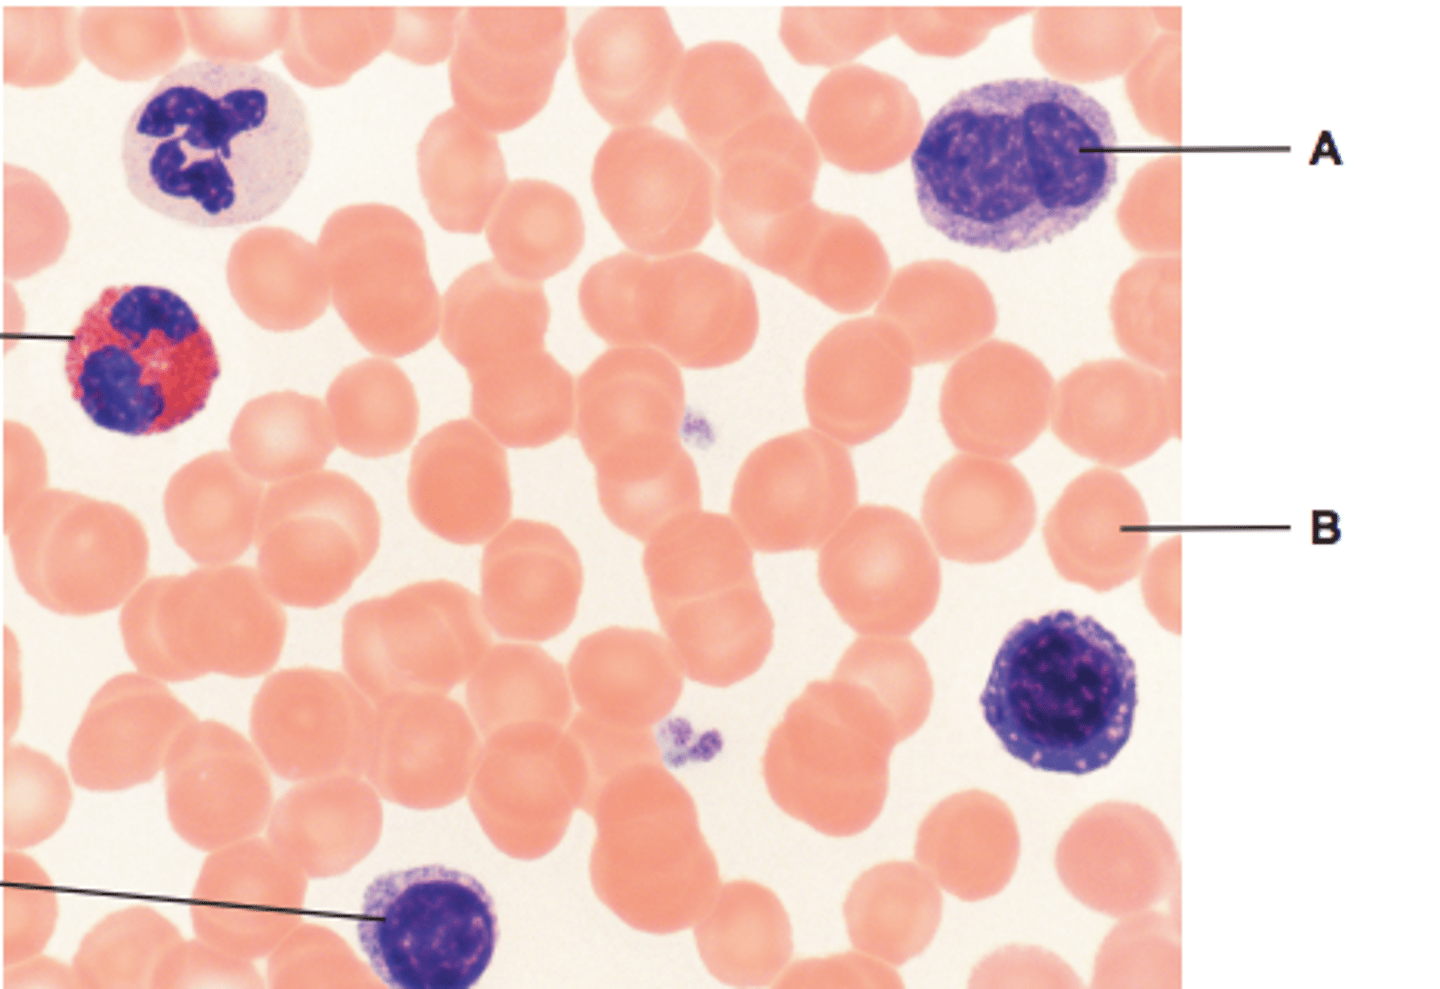

blood smear

identify A and B

lighter colour cells = erythrocytes

darker colour cells = neutrophils